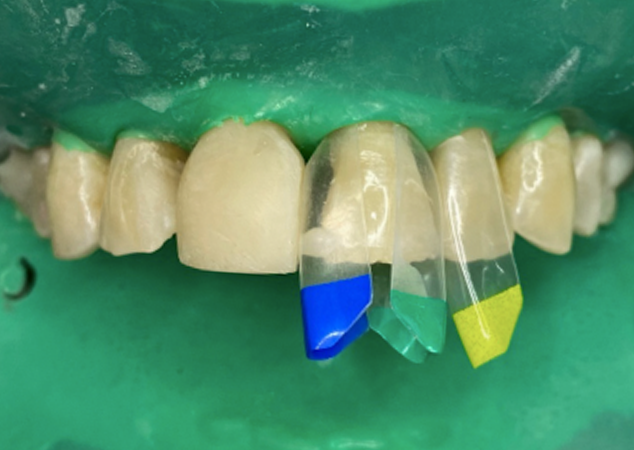

FIG. 7

Les dents sont construites en séquence et réduites à 80 % au fur et à mesure de l'évolution du cas. Notez l'excès de matériau requis sur la dent 22 pour assurer une restauration finale monolithique et sans porosité. Notez la matrice jaune sur la face mésiale de la dent 13 : elle agit comme un bouclier pendant le processus de moulage par injection de la dent 12.

Toutes les dents restantes sont ensuite traitées une par une avec les matrices Bioclear Black Triangle de taille appropriée (Fig. 7), puis moulées par injection et réduites séquentiellement, selon les mêmes principes (Fig. 8).

FIG. 8

La réduction finale est obtenue une fois que toutes les dents du sextant 2 sont moulées par injection.